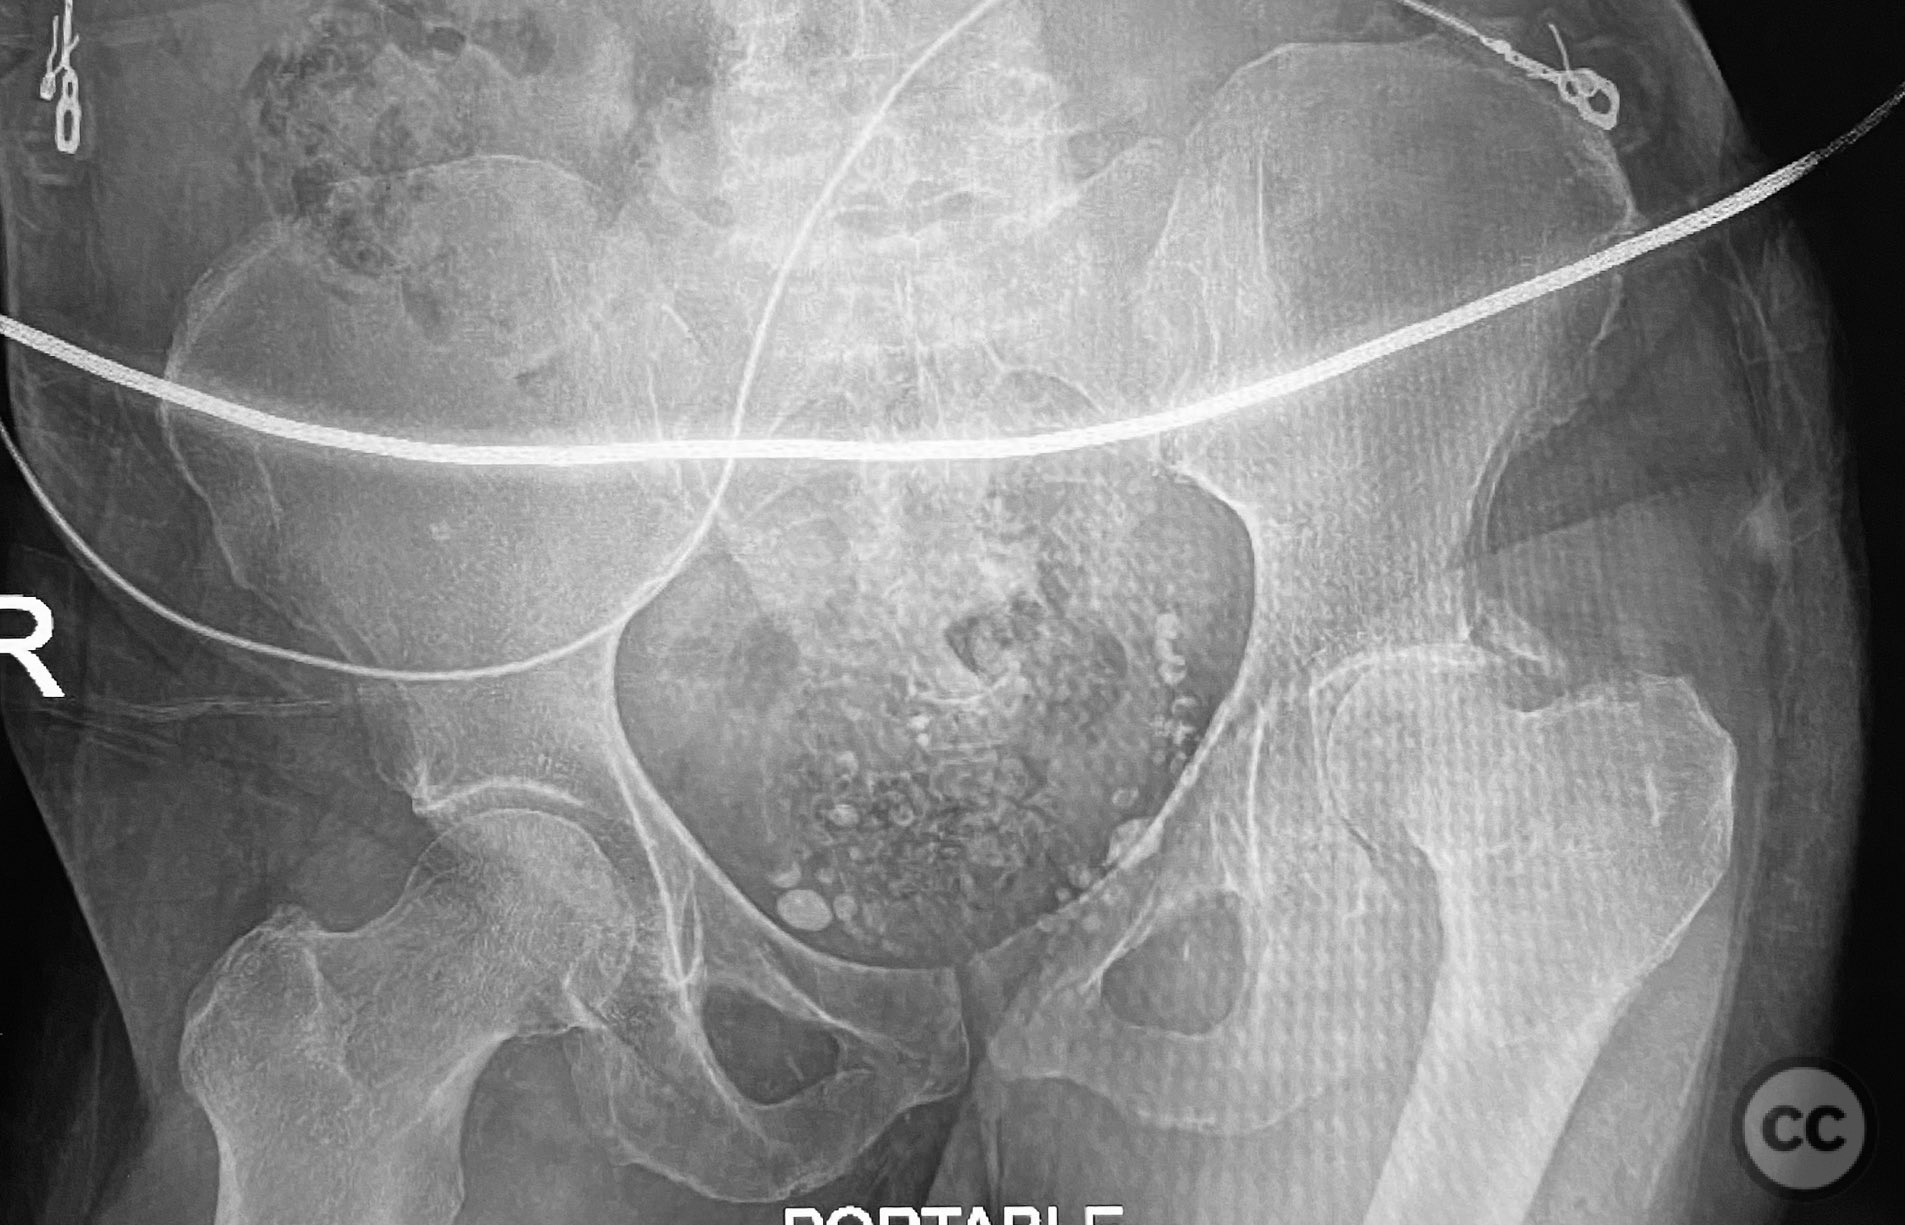

Open Comminuted Iliac Wing Fracture with...

Texas, United States

Pelvis - AO/OTA 6x